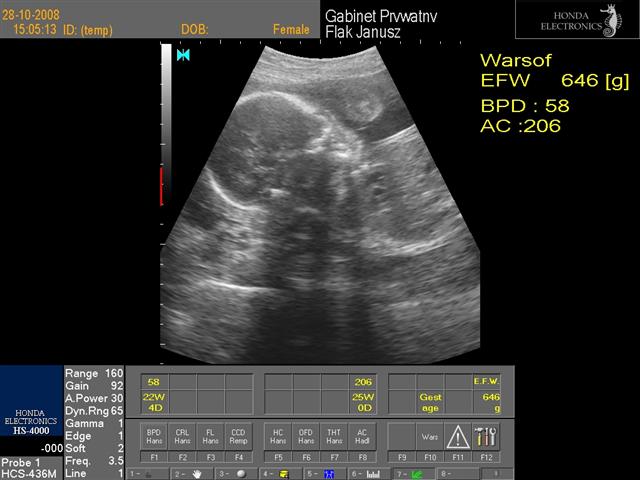

hej dziewczynki świerzo po wizycie wklejam fotki mojej córci(chyba dziewczynka....nie potwierdzone...ułożenie pośladkowe) to juz 24 tc+1 dzień